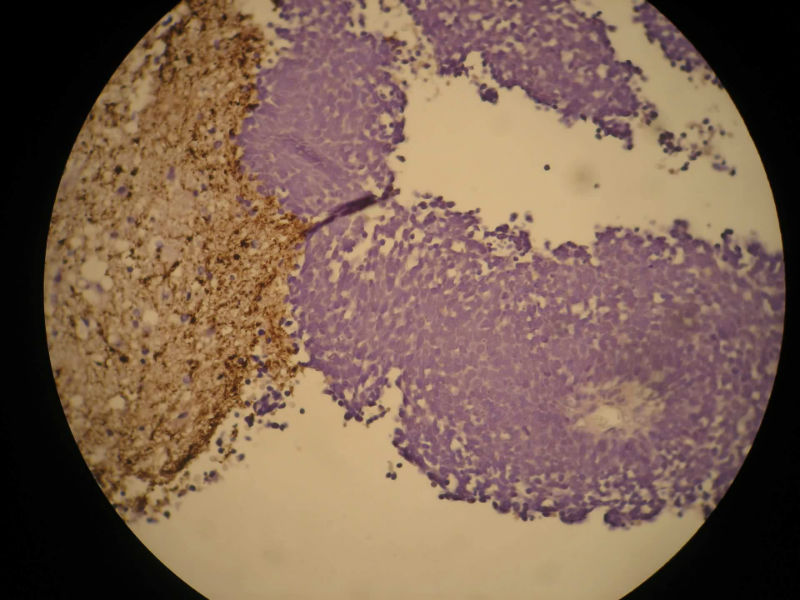

患者,M50Y,左侧肢体乏力半个月,肌力2级

MRI示右顶叶和小脑占位性病变,增强强化明显

术中见鱼肉样质脆,血管丰富,边界不清,部分囊性变,分块切除

大体:碎组织,4.2*3.5*2cm,呈鱼肉状,质嫩软。其间可见少量灰白组织,质韧。

Based on histology and immunohistochemistry, metastatic neuroendocrine carcinoma needs to be ruled out. I suggest TTF-1 stain. Also pay attention to nuclear morphology at high power view and see if it fits small cell carcinoma. It doesn't have to be a primary CNS tumor just because the border appears infiltrative.

谢谢Dr.mjma和楼上各位的指导。形态学符合小细胞癌。我们加做TTF-1,CD56和NSE,下周有结果。